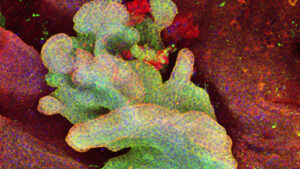

Descobert un nou mecanisme que regula el càncer de pàncrees

Un equip d’investigació, centrat en l’estudi de virus, liderat per Juana Díez, del Departament de [...]